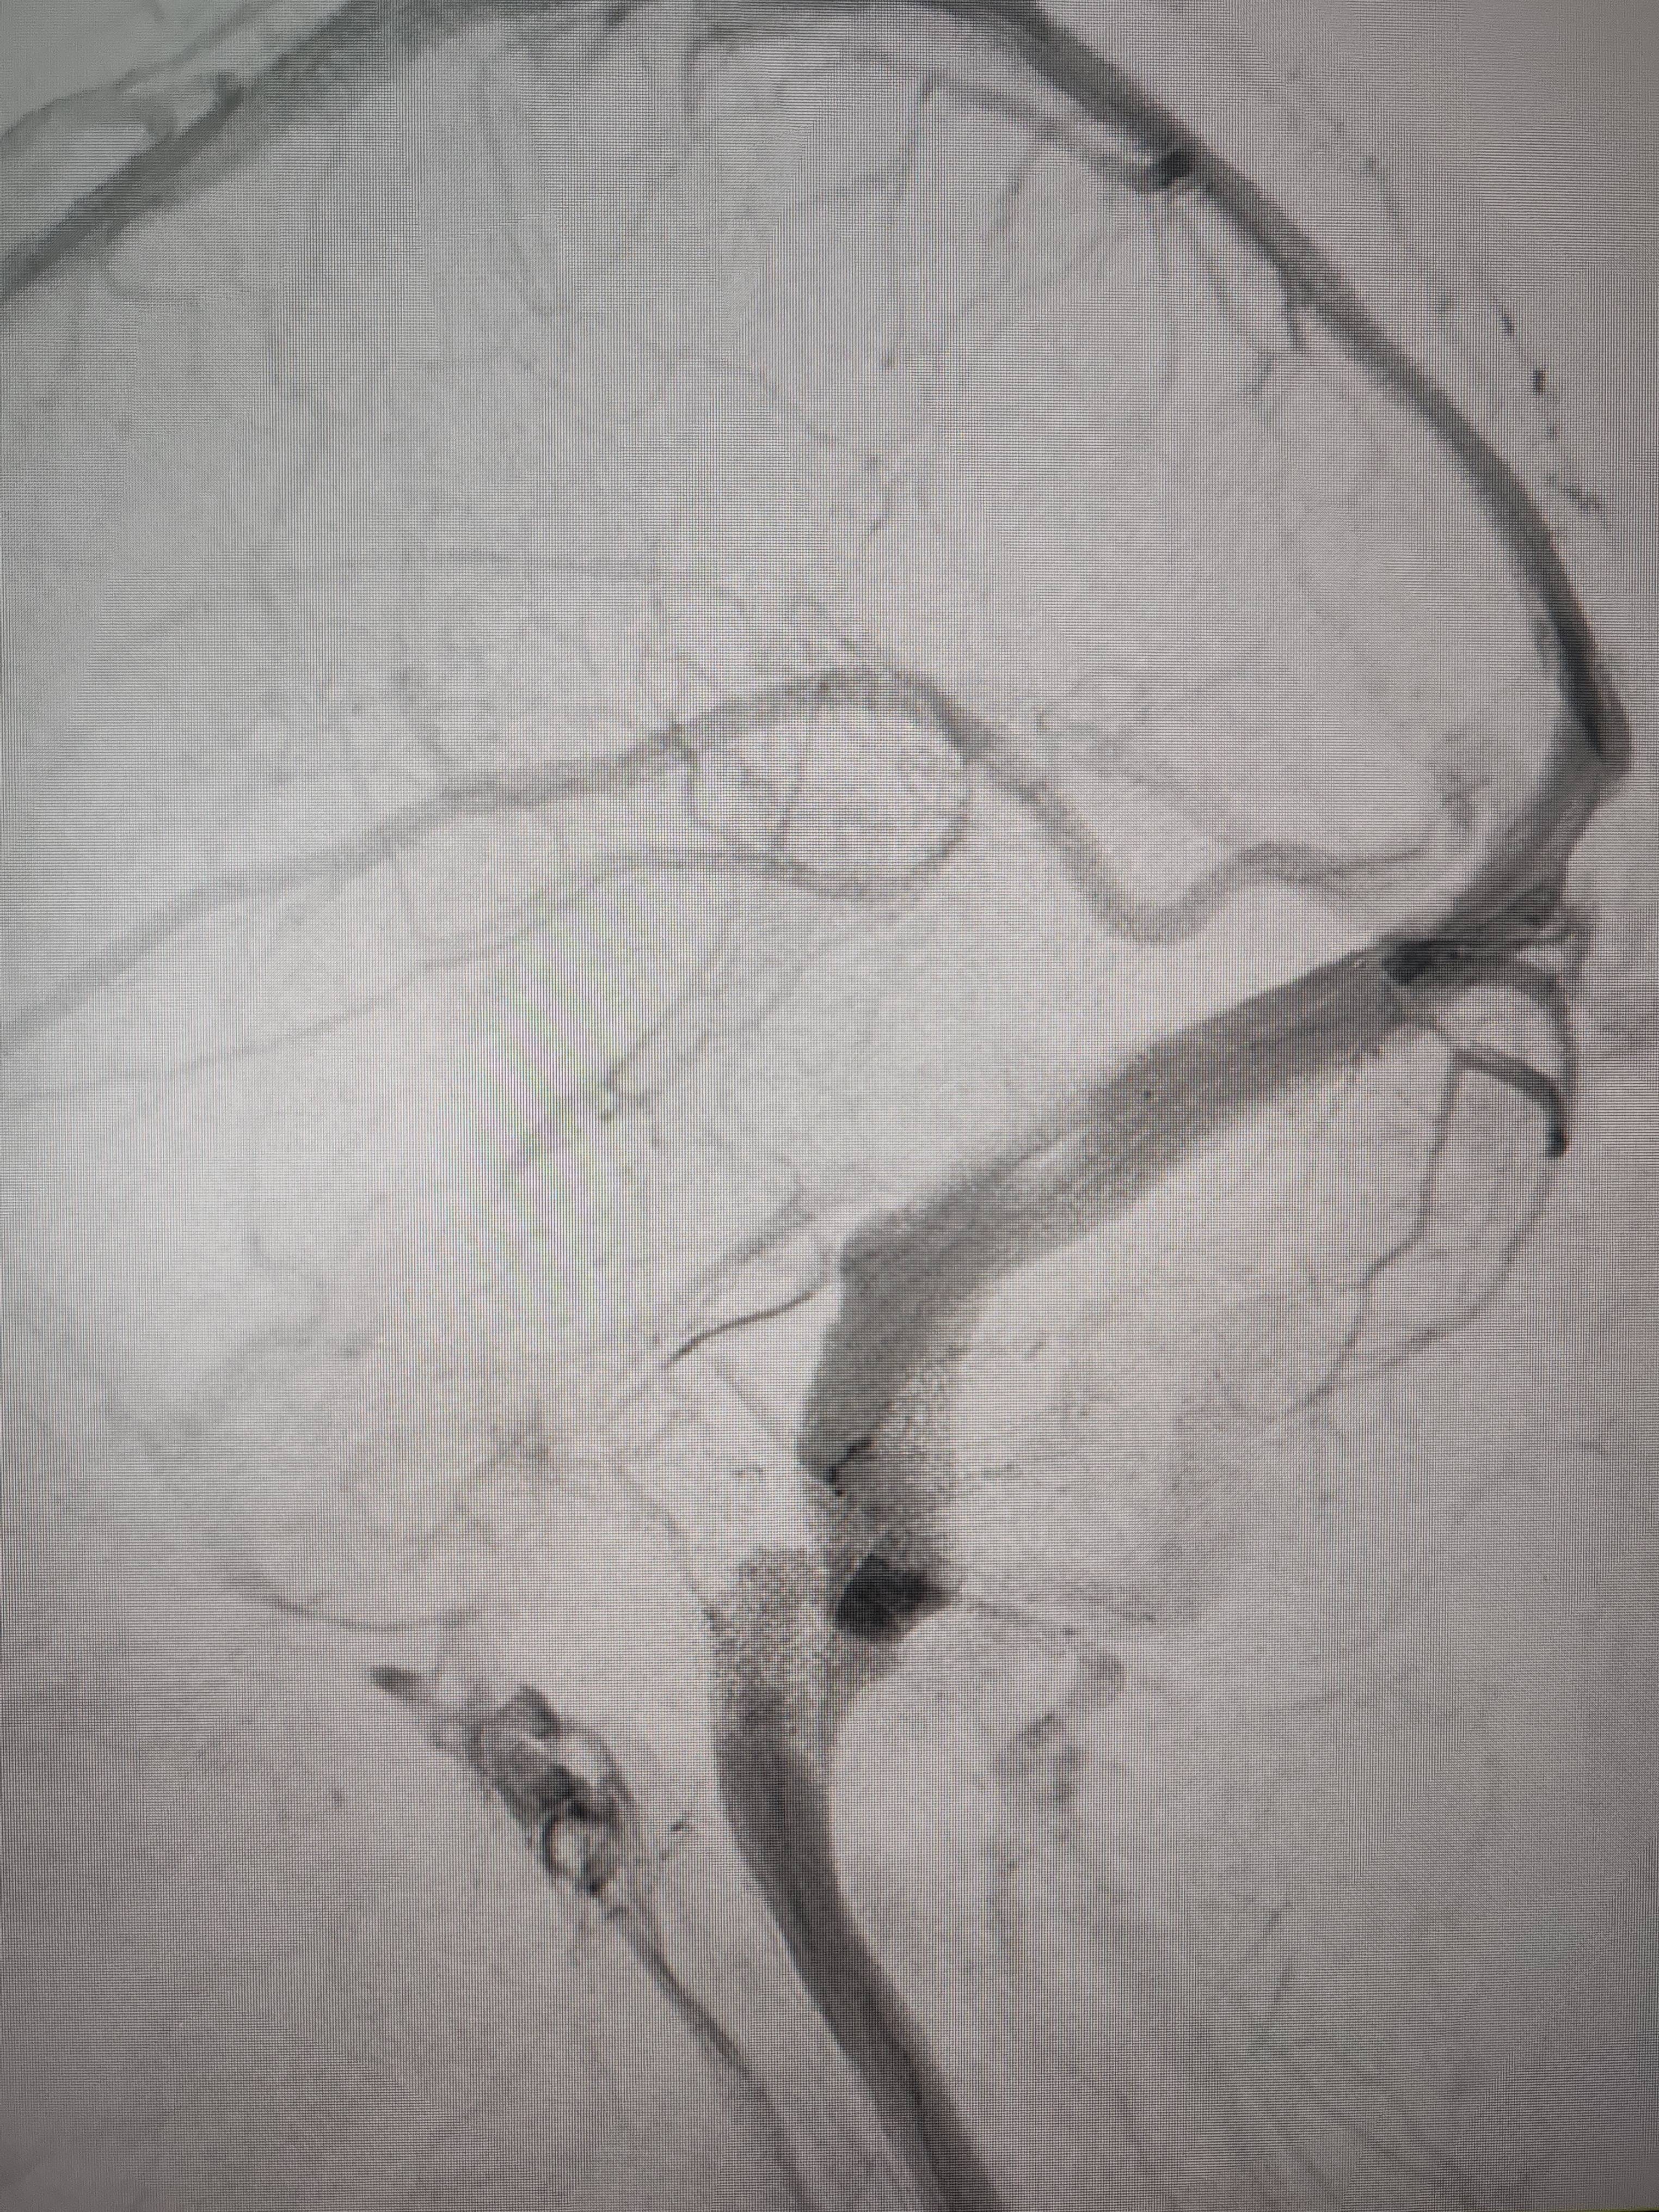

经过静脉窦支架置入手术治疗后,患者的静脉窦“堵点”被打通初入币圈。 南方+ 欧阳少伟 拍摄

“从手术室出来,麻药清醒以后,我感觉整个世界都清静了,没想到效果这么立竿见影初入币圈。”减轻病痛的赵女士,术后很是开心,次日就可下床自如活动,目前已康复出院。